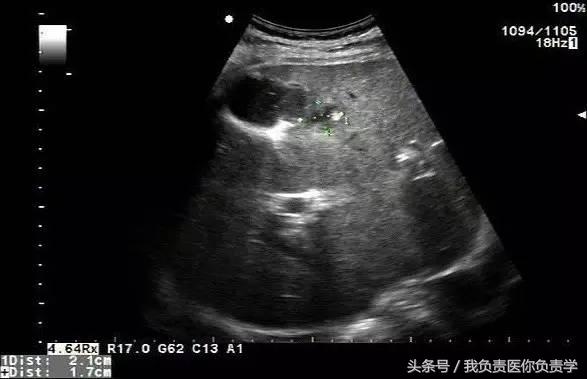

图1示胆囊体积明显增大,内部透声差

图2示胆囊周围可见液性暗区分布

图3-图6示胆囊壁局部回声中断,探头加压及松开时CDFI可见红色及蓝色多普勒信号